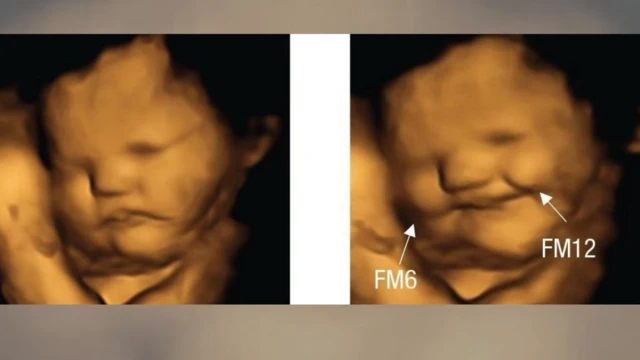

ኣብ ማህጸን ዝርከቡ ዕሸላት፡ ኣደታቶም ካሮት ክበልዓ ከለዋ ‘ፍሽኽ ከምዝብሉ’፡ ሓምሊ ክምገባ ከለዋ ድማ ‘ጽውግ ከምዝብሉ' ኣብ ብሪጣንያ ኣብ 100 ነፍሰጾራትን ዕሸላትን ዝተገብረ ሓድሽ መጽናዕቲ ኣረጋጊጹ።

እቲ ጕጅለ ኣብ መጽሄት ሳይኮሎጂካል ሳይንስ ዘውፅኦ ሓበሬታ ከምዘመልክቶ፡ እተን ኣደታት ነቶም ‘ካፕሱላት’ ካብ ዝውሕጣ ድሕሪ 20 ደቓይቕ፡ ብ4D ኣልትራሳውንድ ክረኣያ እንከለዋ መብዛሕትኦም እቶም ንሓምሊ ዝተቓልዑ ዕሸላት ተጸዊጐም ክብሉ እንከለዉ፣ እቶም ንካሮት ዝተቓልዑ ከኣ ፍሽኽታ ዝመልኦም ነይሮም።

ኣብ ዕሸላት እተን ካብ ክልቲኡ ዘይተወሃበን 30 ነፍሰጾራት ግን ዝዀነ ምላሽ ኣይተራእየን።

ኣብቲ ብኣልትራሳውንድ ዝረአ ጽዋገን ፍሽኽታን "እቲ ንመሪር መኣዛ ምላሽ ዝህብ ዘሎ ምንቅስቓስ ጭዋዳታት ክኸውን ይኽእል'ዩ" ክትብል ተረድእ - ራይስላንድ።